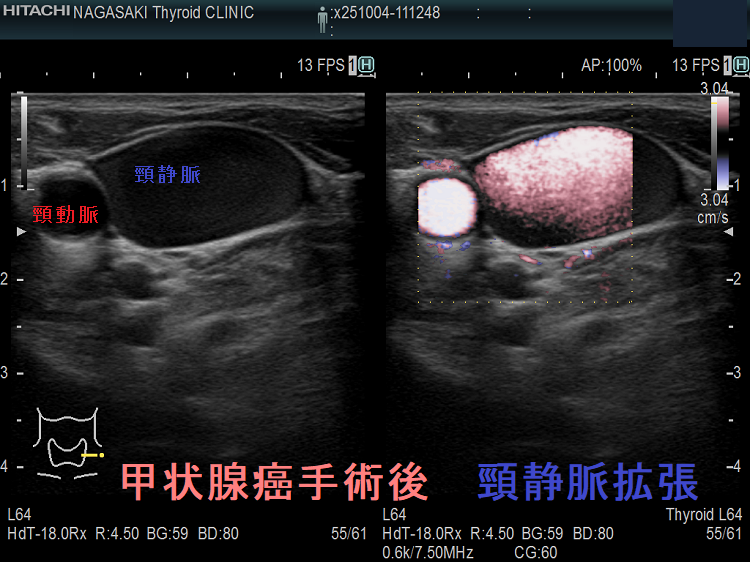

甲状腺癌術後、頸横動脈仮性動脈瘤が生じて破裂する事があります。

報告例は、頚椎後縦靱帯骨化症(OPLL)のため頸部伸展位を取れない状態で外深頸リンパ節を郭清した際、頸横動脈の外膜を傷付け仮性動脈瘤が発生したと推察されます。甲状腺癌手術を終え退院後13日目に頸部痛と左肩甲部から前頸部にかけて腫瘤形成が起きた。画像診断にて頸横動脈瘤とその破裂による大出血と診断し、コ イル塞栓術にて治癒したそうです。(日臨外会誌 67 (10), 2289-2293, 2006)